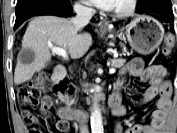

- 单项选择题男,63岁, 肝区疼痛不适1个月,皮肤巩膜无黄染, AFP高于正常,CT所见如图, 最可能的诊断为 ( )